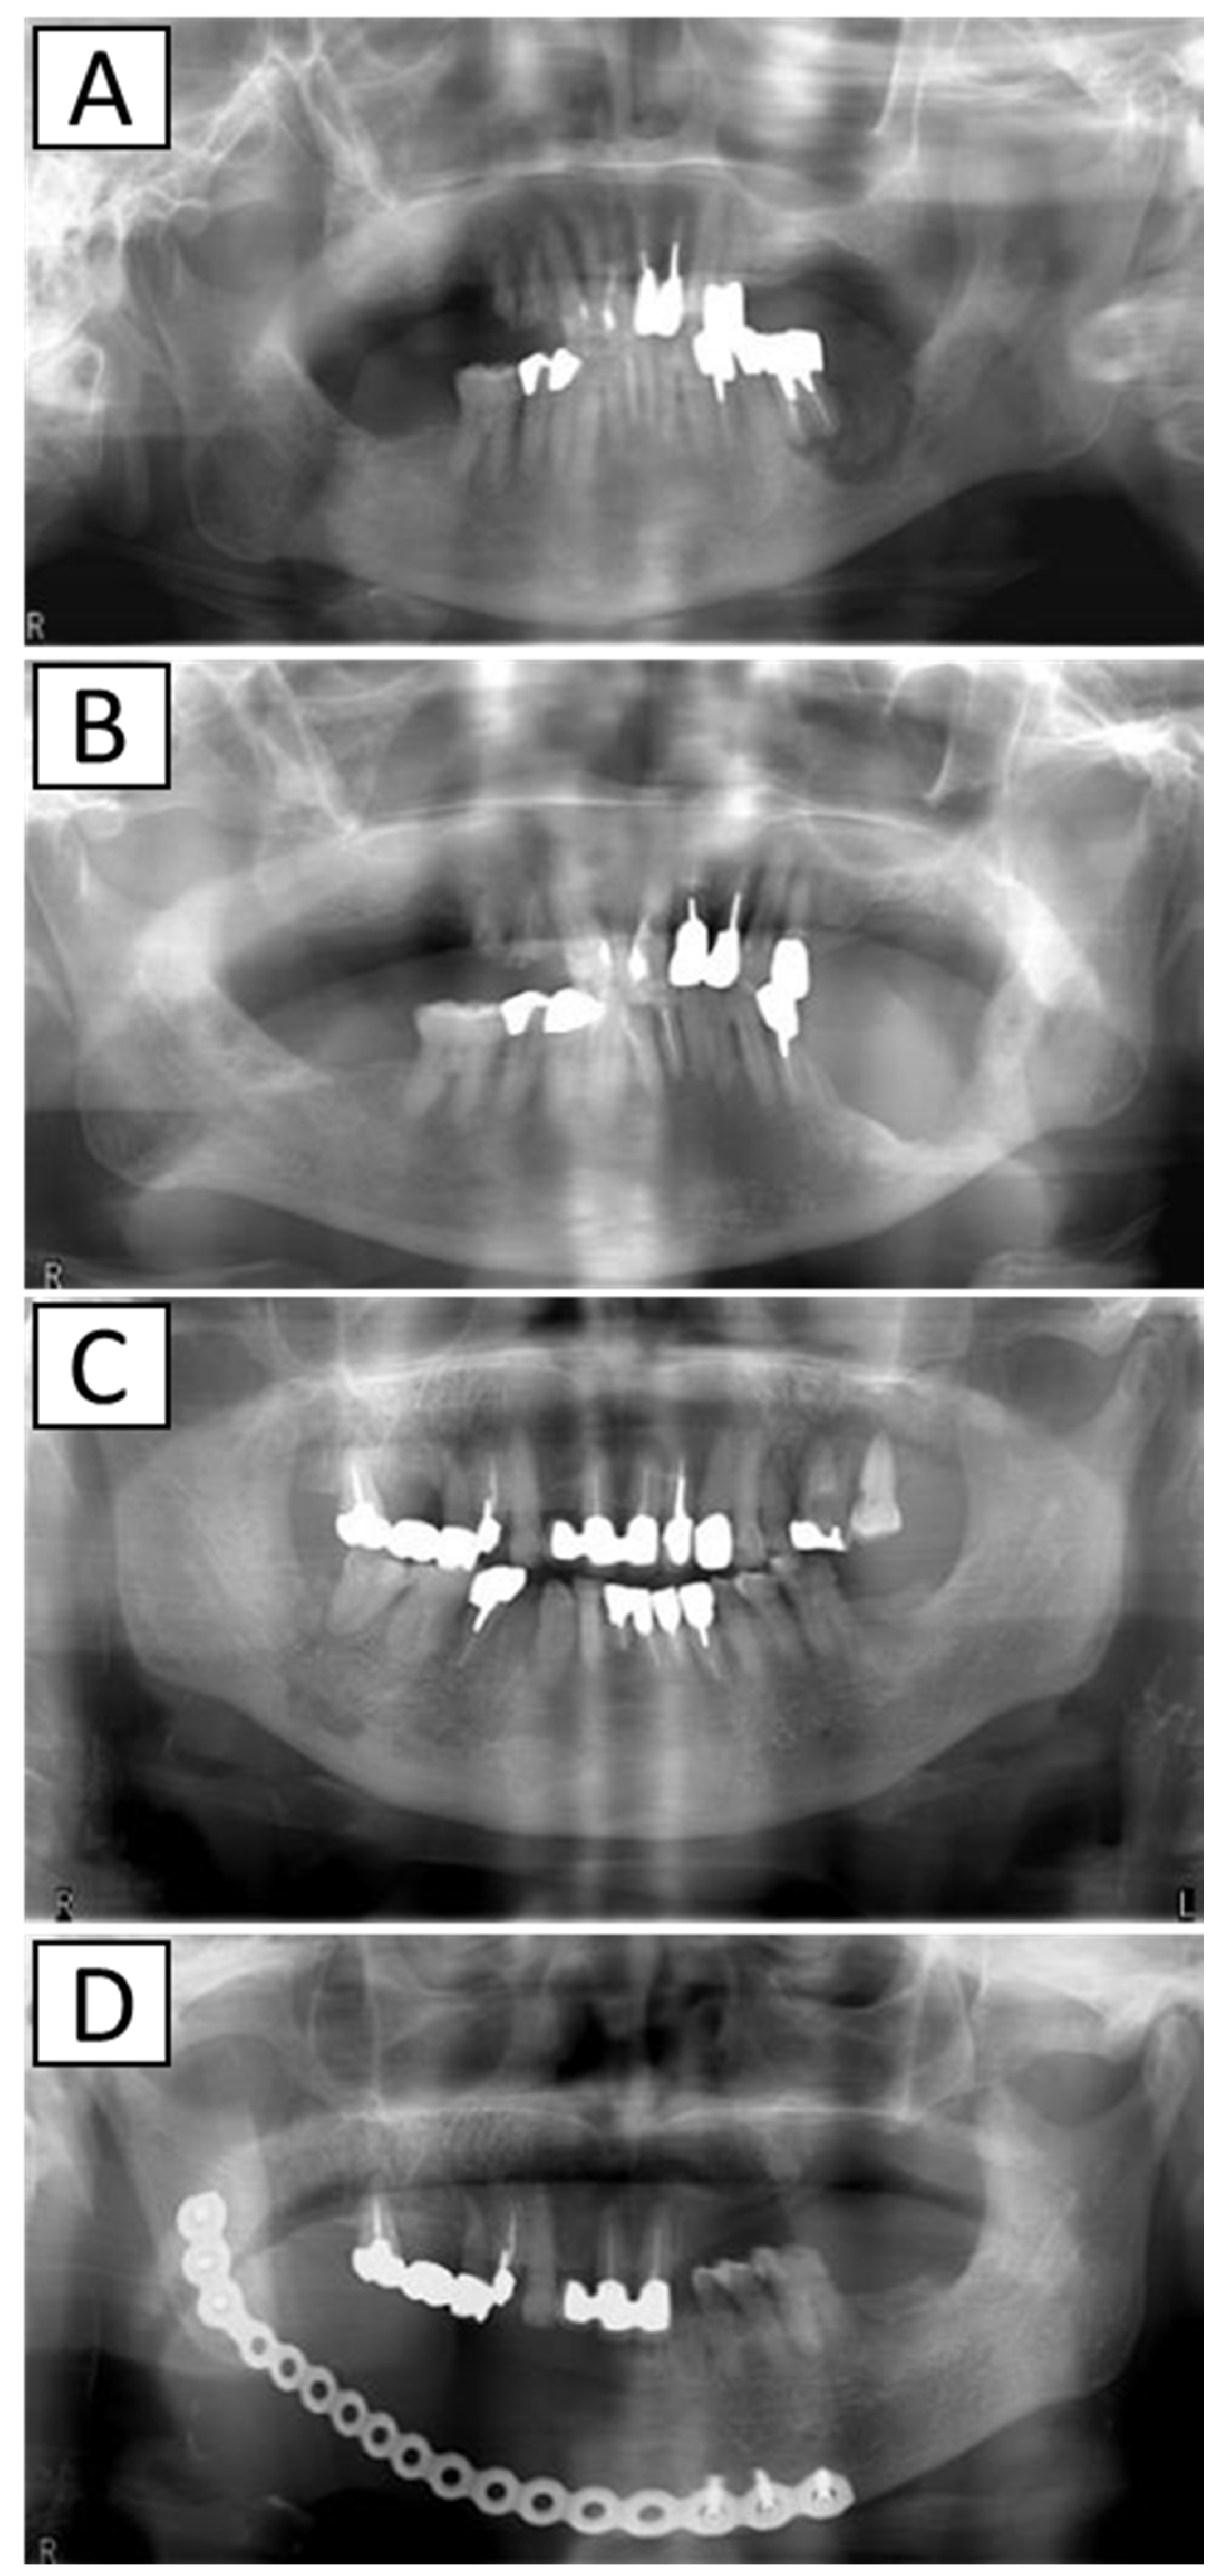

2.1. Impact of AR Drug Holidays on Treatment Outcomes

Figure 1. X-ray images before and after surgery. (A): Before marginal mandibulectomy, (B): after marginal mandibulectomy, (C): before segmental mandibulectomy, and (D): after segmental mandibulectomy.